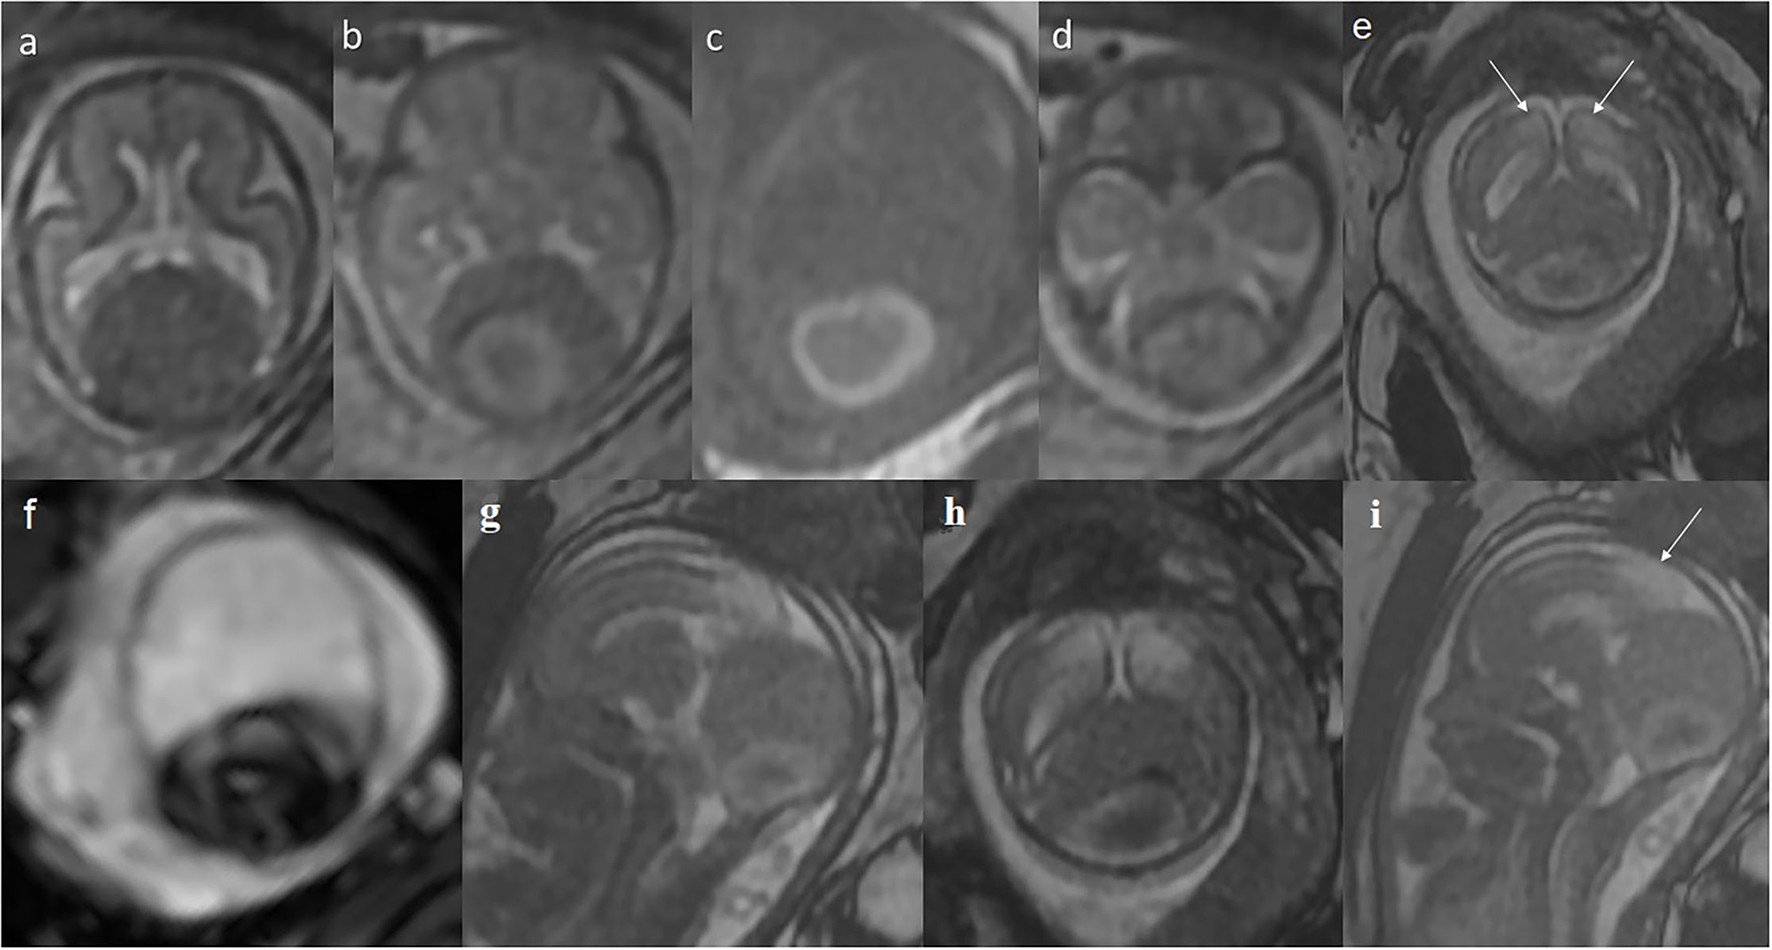

Figure 2

Prenatal MRI at the 23rd gestational week: (a–f) axial, (g,i) sagittal, and (h) coronal plane. Giant widening of the venous sinuses around the sinus confluence. The lesion lifts (h) and displaces the cerebral hemispheres apart (a,b) and compresses and displaces the posterior cranial fossa structures forward (d,g), with the brain stem pressed against the clivus (g). A thrombus (c) containing hemosiderin (g) inside. (e,i) Abnormal T2-hyperintensity of the posterior-medial parts of the cerebral hemispheres is appreciated (arrows) in FIESTA, indicating ischemia/edema caused by the huge mass of sinus ectasia.

Thrombus developing within the venous sinus malformation may result in brain damage in the ischemic mechanism (5, 7). A potential mechanism explaining the absence of neurological complications may be associated with the anastomoses formation that ensure proper venous blood drainage. In our patient, the abnormal vessels were found on postnatal MRI; however, early brain ischemia must have occurred. The fetal MRI at the 23rd GW shows T2-hyperintensity in the posterior parasagittal parts of both cerebral hemispheres, most likely representing ischemic insult, sufficiently distant in time not to restrict diffusion (Figures 2e,g–i). To the best of our knowledge, we present the first report of polymicrogyria co-existing with giant venous sinus ectasia with thrombus. Taking into consideration all findings in the prenatal imaging (dural abnormality and signs of brain ischemia) and the available knowledge of early ischemia as one of the possible causes of PMG (8), the case of our patient seems to prove the causative association of thrombosed giant dural sinus ectasia with PMG. Moreover, the patient presented with bilateral parasagittal parieto-occipito-frontal polymicrogyria not described before. The most resembling entity found in the literature was bilateral parasagittal parieto-occipital polymicrogyria (9).